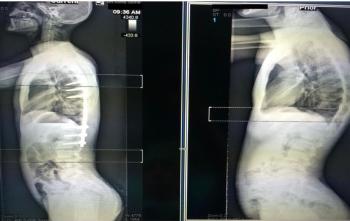

Bel Fıtığı (Lomber disk hernisi)

Disk materyali iki omur cismi arasında dışarıda görece olarak daha sert bir kılıf, içeride ise jel kıvamında yumuşak doku kısımlarından oluşur. Bir y...

Günümüzdeki modern tanı yöntemlerinden olan Manyetik Rezonans(MR) ile bel fıtığı teşhisi kolaylıkla konulmakta ve derecesi belirleneb...

Bel fıtığı ameliyatlarındaki amaç fıtıklaşan diskin temizlenesi ve sinir üzerindeki basıyı kaldırmaktır.Açık diskektomi: Genellikle genel anestezi ...